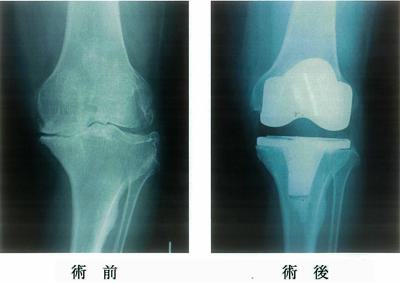

74歳の女性。5年前から左膝痛が出現し、徐々に増悪して歩行が困難となったため左膝の手術を受けた。術前と術後のエックス線写真を示す。術前の所見で認められるのはどれか。2つ選べ。

1

骨棘形成

2

骨融解像

3

外反膝変形

4

特発性骨壊死

5

関節裂隙の狭小化

74歳の女性。5年前から左膝痛が出現し、徐々に増悪して歩行が困難となったため左膝の手術を受けた。術前と術後のエックス線写真を示す。術後の理学療法で適切でないのはどれか。

術後2日目から大腿四頭筋のセッティングを行う。

術後3日目から膝関節の可動域訓練を行う。

術後7日目から足関節の自動運動を行う。

術後10日目から荷重歩行訓練を行う。

退院後も屋外で杖を使用する。